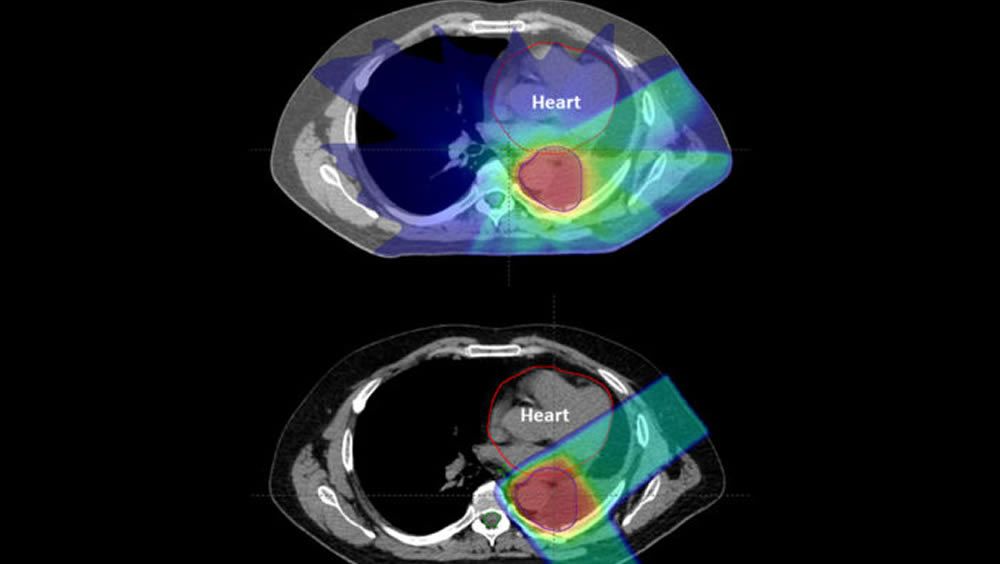

La radiación de fotones generalmente utiliza múltiples haces de rayos X para atacar a un objetivo tumoral, pero inevitablemente deposita radiación en los tejidos normales más allá del objetivo, dañando potencialmente esos tejidos cuando el rayo sale del cuerpo. La terapia de protones, una radiación alternativa, funciona de manera diferente, dirigiendo protones cargados positivamente hacia el objetivo del tumor, donde depositan la mayor parte de la dosis de radiación, con una radiación residual mínima administrada más allá del objetivo, reduciendo potencialmente los efectos secundarios y el daño al tejido circundante.